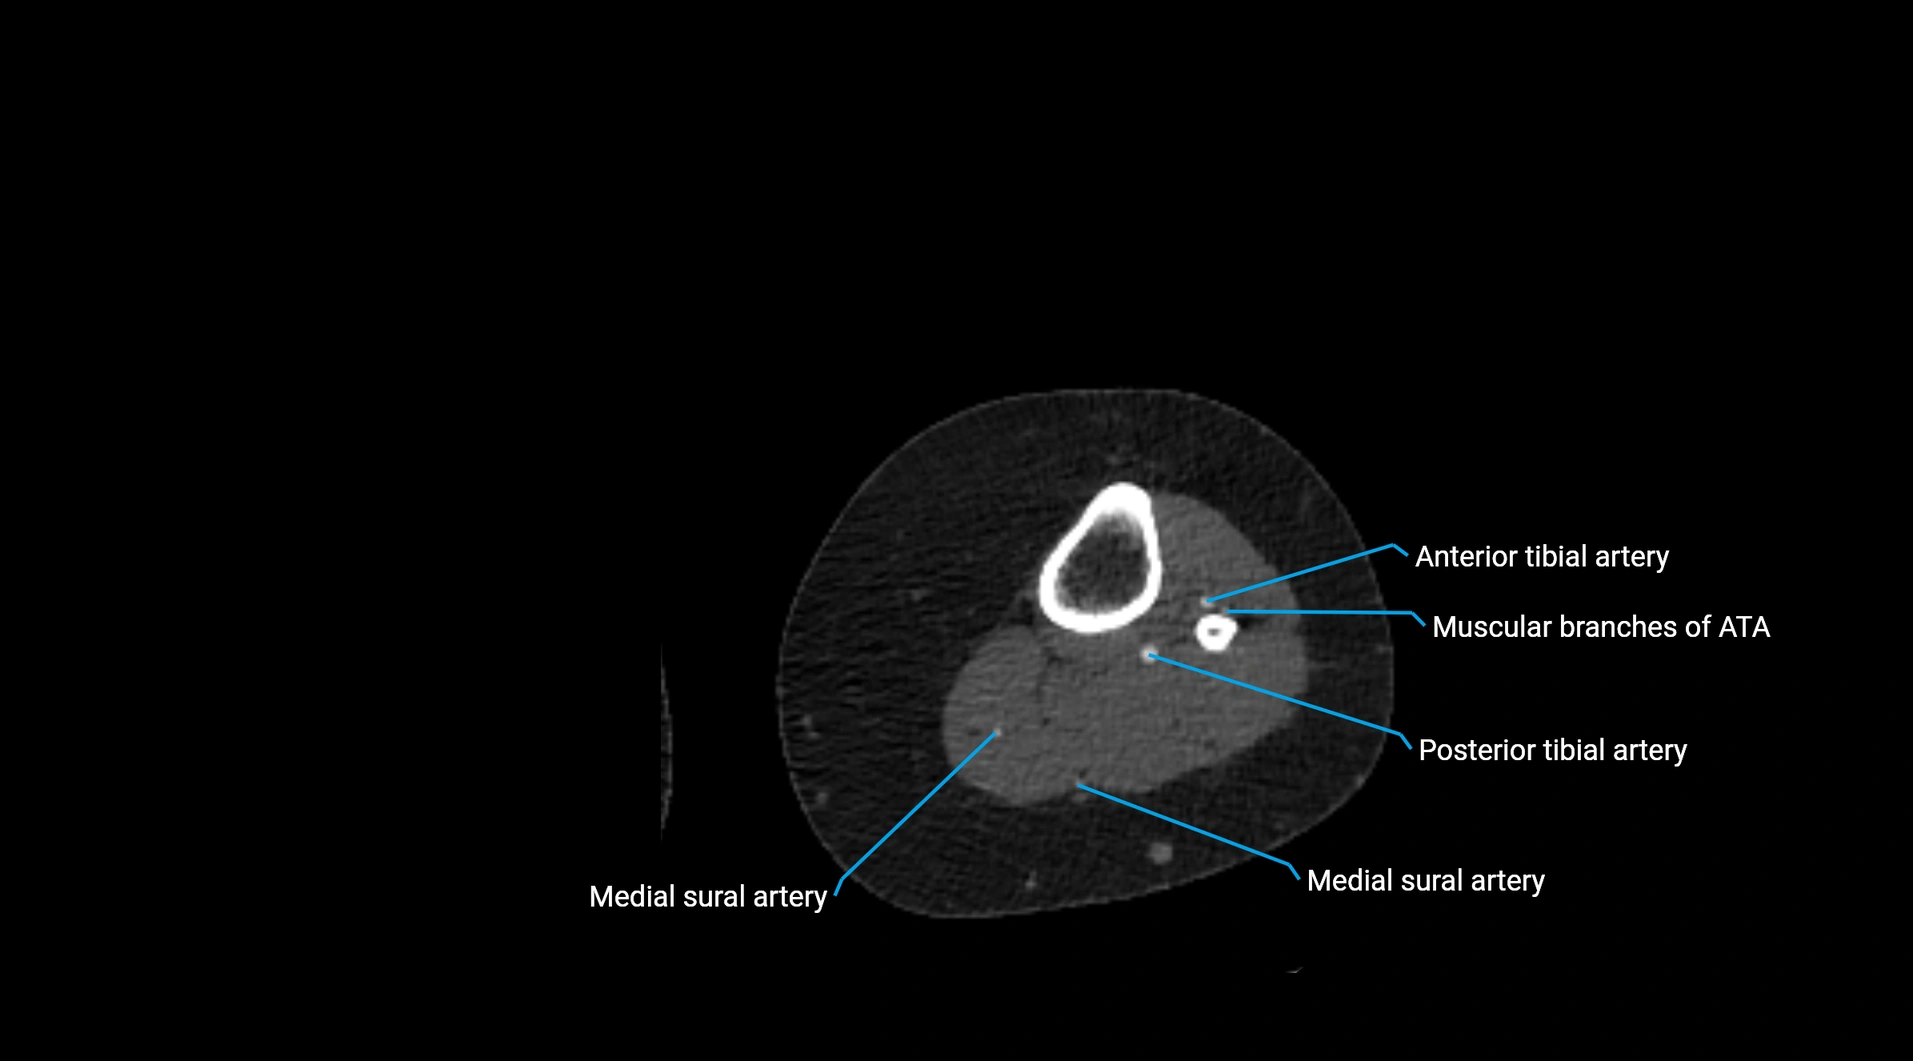

CT Appearance

Non-contrast CT:

• Appears as a tubular soft tissue structure anterior to vertebral bodies

• Calcified atherosclerotic plaques appear as hyperdense foci along the wall

• Useful for screening abdominal aortic aneurysm (AAA) size and mural calcification

Contrast-enhanced CT (CTA):

• Gold standard for abdominal aortic imaging

• Provides excellent detail of lumen, wall, aneurysm, thrombus, and branch vessels

• Multiplanar and 3D reconstructions help in aneurysm measurement, stent graft planning, and dissection evaluation

• Detects acute rupture, traumatic injury, or occlusion with high sensitivity